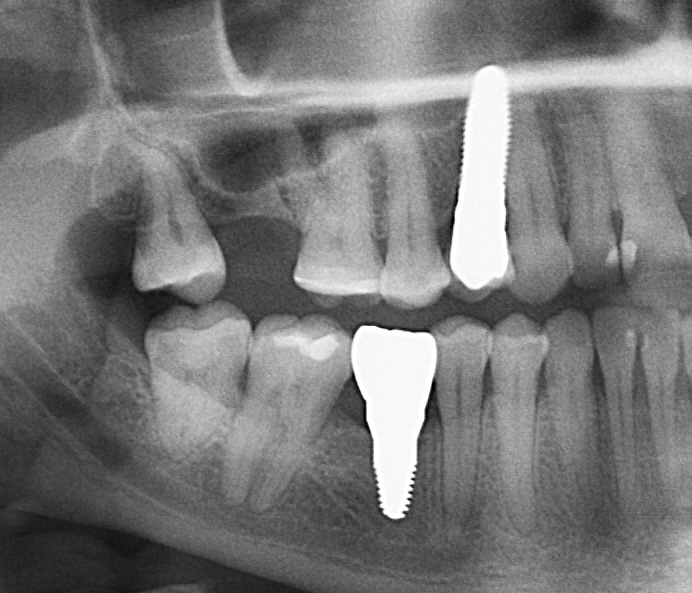

The

patient had his bottom six removed years ago. The teeth had become misaligned

and orthodontic therapy was used to correct the bite of the entire dentition.

After 6 months of successful

orthodontic treatment, we were finally able to place the implant and the

provisional crown. After 4 months of ingrowth, aligners were removed and a full

ceramic crown was placed. The treatment was successfully completed!✋🏽😉